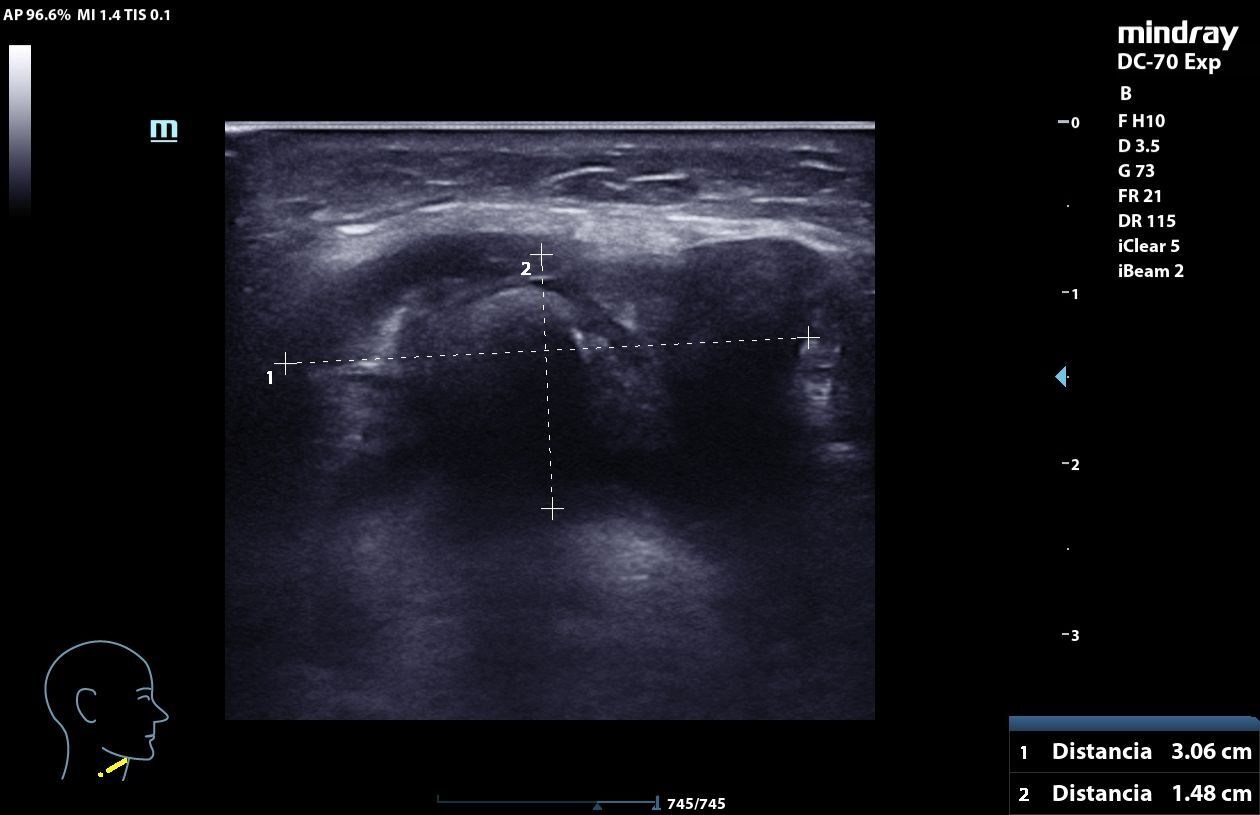

A nivel medial del cuello, por encima del cartílago cricoideo, masa heterogénea, mal delimitada, con calcificaciones internas que generan sombra acústica posterior, elementos hiperecogénicos y algunas zonas anecoicas con refuerzo posterior, con captación en Doppler. La lesión mide 3,06 x 1,48 x 2,78 cm y se mueve con la deglución. En relación con quiste tirogloso complicado o proceso neoformativo.